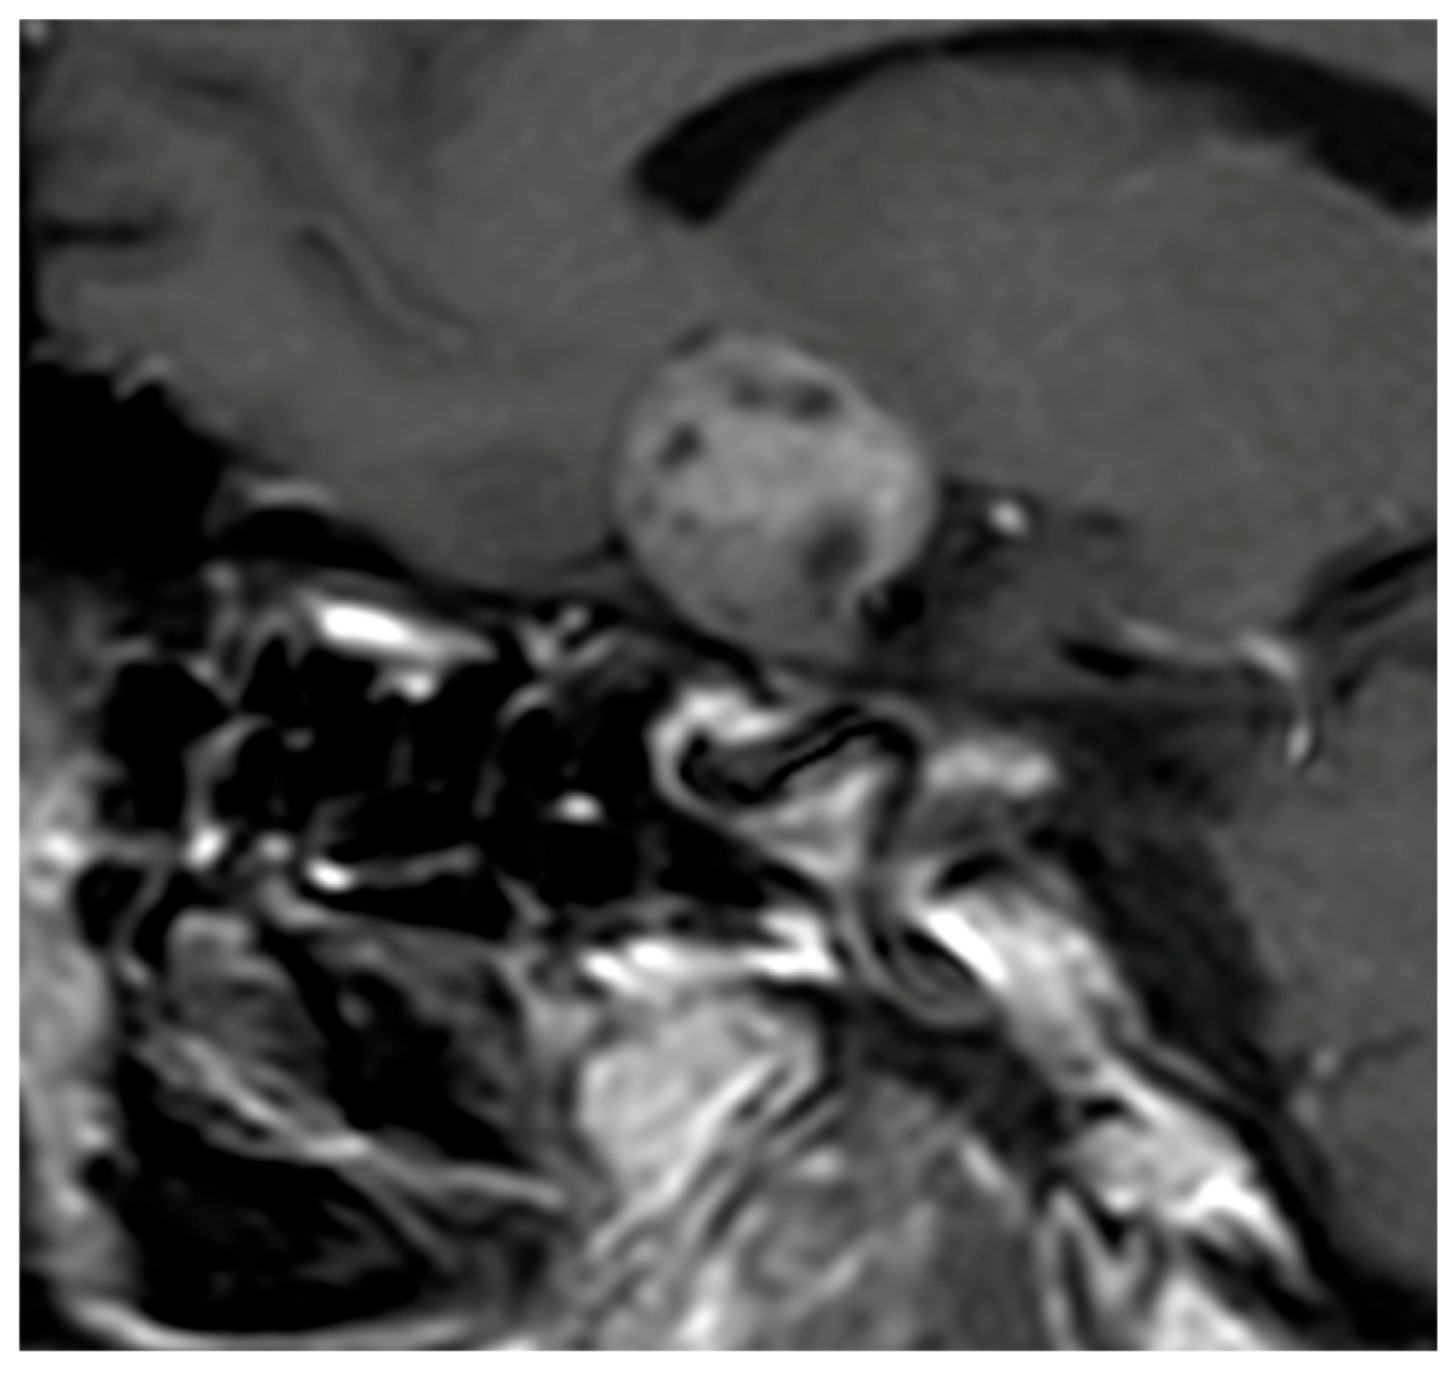

Signal characteristics on MRI further reinforce this opposition. Hypophysitis usually exhibits an isointense signal on both T1- and T2-weighted sequences [70,71], indicative of homogeneous inflammatory tissue without necrosis or cystic degeneration. In contrast, NFPMA often show variable signal intensities, with possible T1 hypersignal due to intratumoral hemorrhagic components [37] and frequent T2 hyperintensity related to cystic or necrotic transformation [37,72]. Flanagan et al. [8] and Wright et al. [38] reported T2 hypersignal in only 5 to 8% of hypophysitis, as opposed to 25% in macroadenomas, underscoring the relative uniformity of inflammatory lesions (Figure 2).

Figure 1. Sagittal T1-weighted image after Gadolinium injection showing a heterogeneous enhancement of the pituitary mass consistent with a NFPMA.